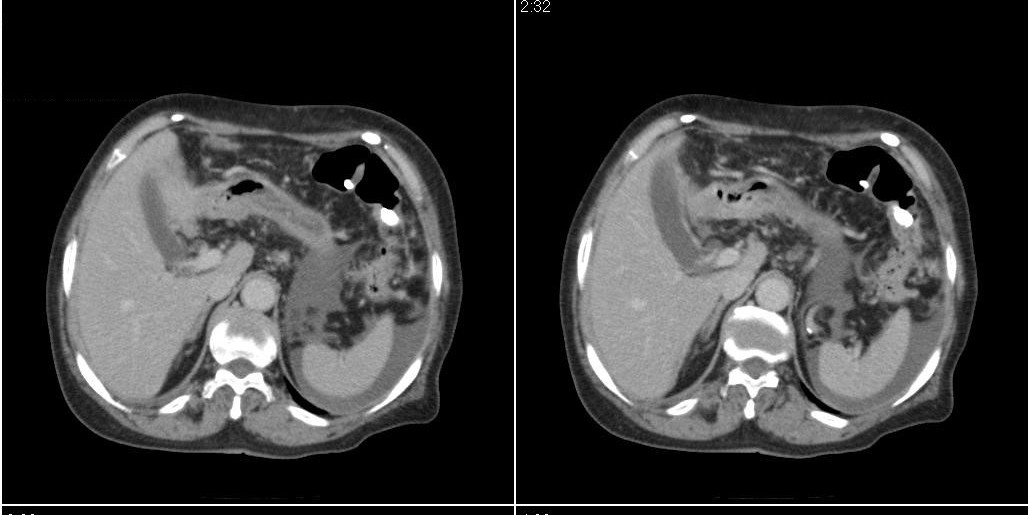

标题: CT24555:82岁女性,因为反复胸腹部积液进行CT检查,结果如下 [打印本页]

标题: CT24555:82岁女性,因为反复胸腹部积液进行CT检查,结果如下

胆囊有问题么,是结石么?胆囊内异常密度平扫30hu左右,增强各期无变化。

胆囊内稍高密度影,无强化,胆囊壁增厚,周围见低密度影,右侧膈肌角及脾周水样密度,支持胆囊泥沙样结石,胆囊炎、胆囊窝积液,胸腹水。

支持胆囊泥沙样结石,做个b超对结石更有特异性。

1)胆囊炎,胆结石;胆囊新生物待排。2)胆囊窝积液。3)腹水。4)右侧少量胸腔积液。